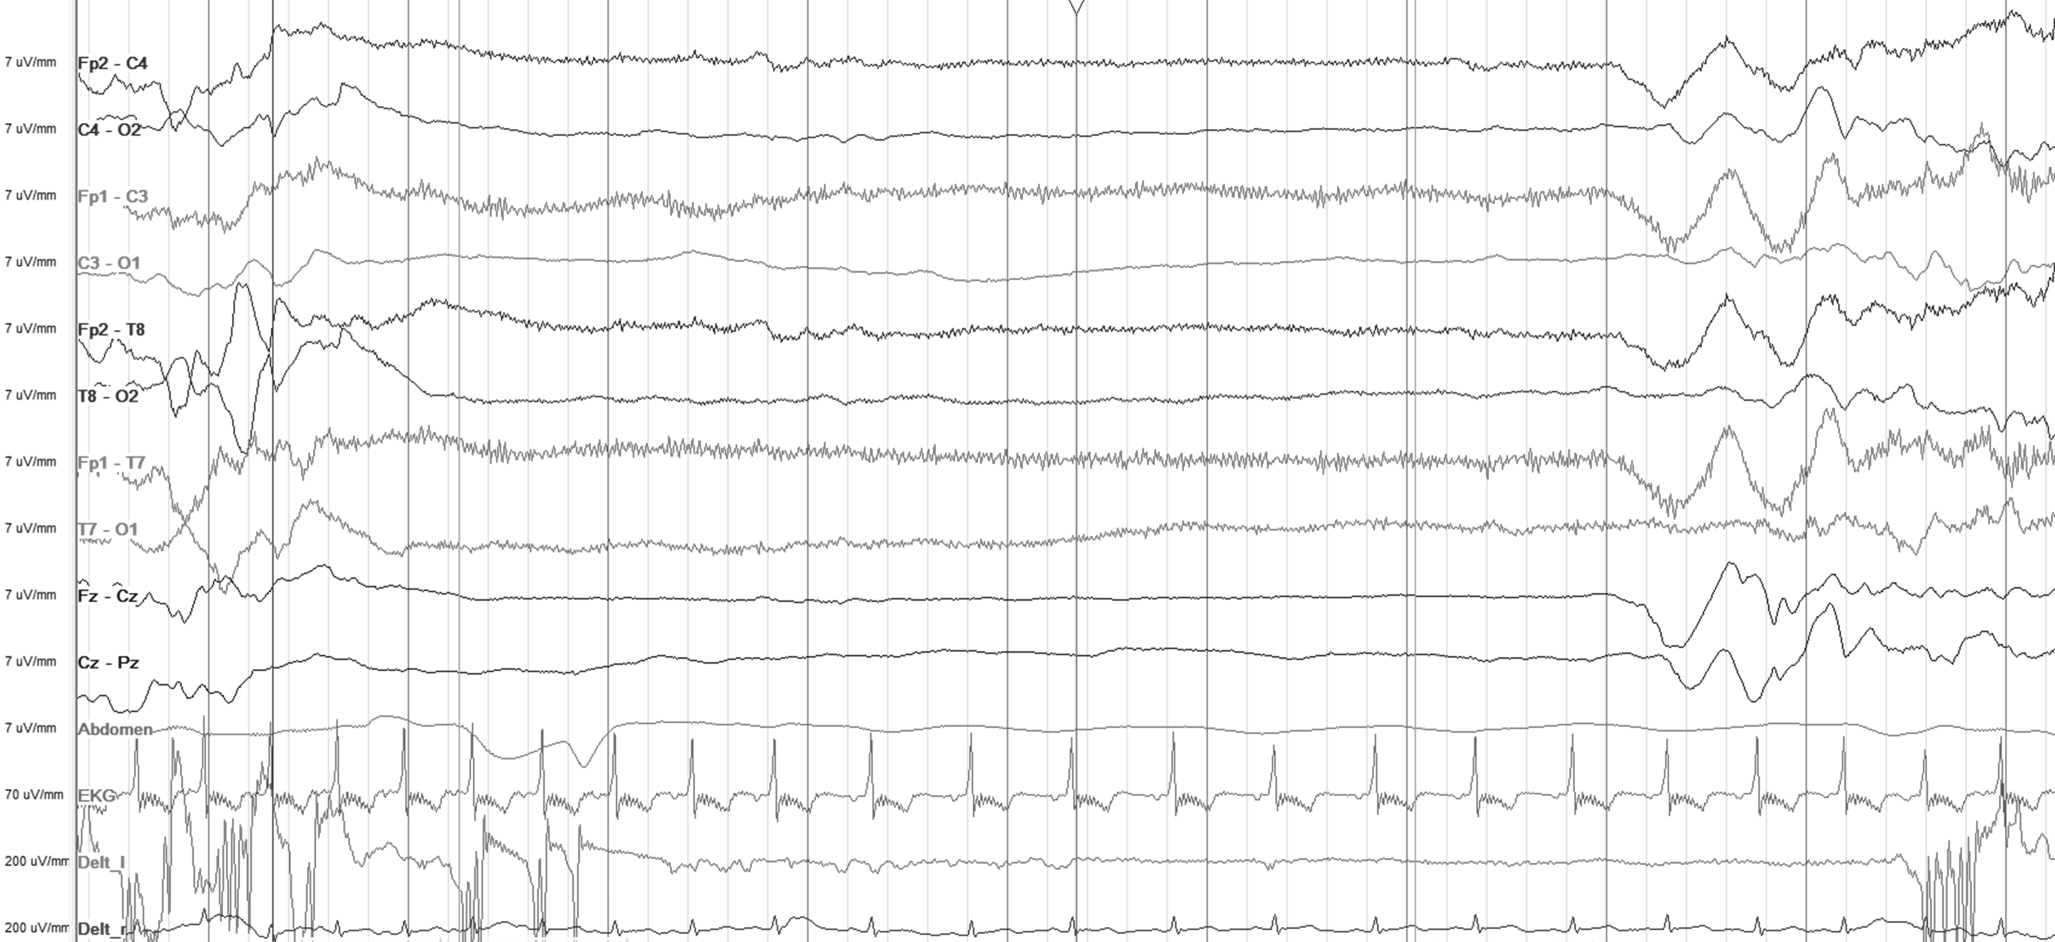

Fig. 4

Ictal electroencephalogram (age 3 days, amplitude 7 µV): sequential seizure with a a tonic phase, b a clonic phase (first half of the image, bilateral spikes and waves) followed by another tonic phase (second half of the page, bilateral flattening of amplitude and rapid activity), and c an autonomic phase with apnea (note absence of abdominal movement in the second half of the image) due to a KCNQ2 variant

Fig. 5

Interictal electroencephalogram (age 6 weeks, amplitude 10 µV): increased beta activity due to PAFAH1B1 (LIS) variant. Clinical presentation: focal clonic seizures and behavioral arrest

Fig. 6

Interictal electroencephalogram (age 4 months, amplitude 10 µV): deterioration of the EEG with hypsarrhythmia, partly fragmented. Clinical presentation: spasms

Fig. 7

Interictal electroencephalogram (age 4 months, amplitude 10 µV): diffuse slowing with superimposed sharp waves and sharp-and-slow wave complexes in the right hemisphere due to a CDKL5 variant. Clinical presentation: tonic seizures

Fig. 8

Interictal electroencephalogram (age 6 weeks, amplitude 7 µV): discontinuous background, intermittent burst-suppression (not shown), and multifocal spikes due to a compound heterozygous RARS2 variant. Clinical presentation: focal clonic seizures, lactic acidosis, hypoglycemia